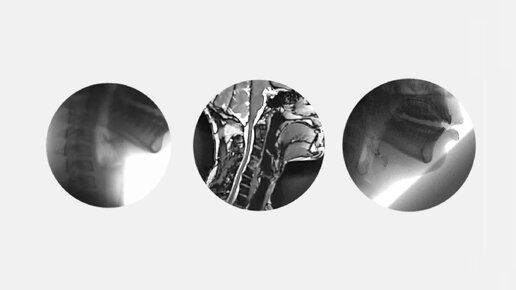

Голосовой аппарат